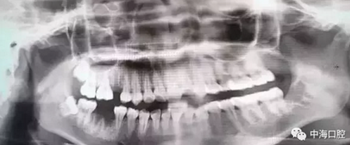

由于智齒的生長位置特殊,導致了拔除難易不同,如智齒出現(xiàn)橫著長或者靠近牙神經的話,則難度會較高,一般人只需拍個口腔全景片,但相對于智齒靠近神經管的情況,還可能需要拍CT,這都很考驗牙醫(yī)的技術。

下面這兩張圖,據(jù)說拔牙費時1.5小時,收費14000元。